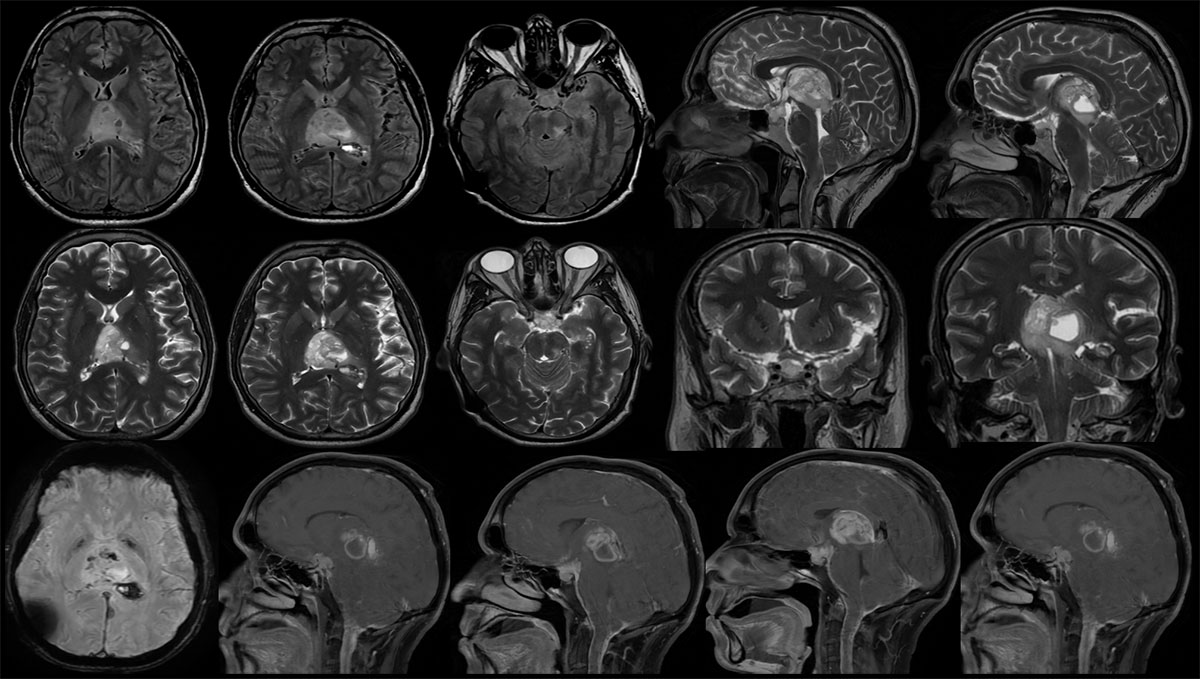

MRI:

- Heterogeneous, multiloculated solid-cystic lesion with calcifications and haemorrhage in pineal region causing mass effect of brainstem, the solid component shows intense enhancement and the cystic areas show peripheral enhancement.

- Similar solid lesion seen in sellar-suprasellar region, shows intense contrast enhancement.

- Multifocal areas of nodular and smooth leptomeningeal enhancement predominantly along the cerebral hemispheres (L>R).

- There is leptomeningeal enhancement along the visualised cervical cord – leptomeningeal drop metastasis.